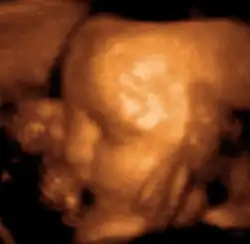

Medical ultrasound is an ultrasound-based diagnostic medical imaging technique used to visualize muscles, tendons, and many internal organs to capture their size, structure and any pathological lesions with real time tomographic images. Ultrasound has been used by radiologists and sonographers to image the human body for at least 50 years and has become a widely used diagnostic tool.[38] The technology is relatively inexpensive and portable, especially when compared with other techniques, such as magnetic resonance imaging (MRI) and computed tomography (CT). Ultrasound is also used to visualize fetuses during routine and emergency prenatal care. Such diagnostic applications used during pregnancy are referred to as obstetric sonography. As currently applied in the medical field, properly performed ultrasound poses no known risks to the patient.[39] Sonography does not use ionizing radiation, and the power levels used for imaging are too low to cause adverse heating or pressure effects in tissue.[40][41] Although the long-term effects due to ultrasound exposure at diagnostic intensity are still unknown,[42] currently most doctors feel that the benefits to patients outweigh the risks.[43] The ALARA (As Low As Reasonably Achievable) principle has been advocated for an ultrasound examination – that is, keeping the scanning time and power settings as low as possible but consistent with diagnostic imaging – and that by that principle nonmedical uses, which by definition are not necessary, are actively discouraged.[44]